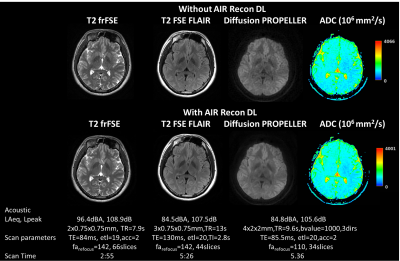

Figure 1 shows the silent 3D ZTE-based localizer, T1-weighted MPRAGE and MRA images from one volunteer before and after applying DL-based image reconstruction. Figure 2 shows representative images from one volunteer for the 2D ART FSE based. T2-weighted, T2-FLAIR and diffusion-weighted Propeller before and after DL-based image reconstruction are included. ADC was also computed from the diffusion-weighted images. Figure 3 shows the results from LoopingStar (T2*, QSM, SWI and fMRI) and the silent parameter mapping sequence (PD, T1 and T2) for one volunteer. The in-bore ambient acoustic noise in the absence of scanning was 67.2 dBA (LAeq) and 91.5 dB (Lpeak). All sequences presented lower than 100dBA mean acoustic noise (LAeq). Both participants indicated that the scan session was pleasant.

Figure 2: 2D FSE-based scans utilizing the acoustic noise reduction technique (ART), including Cartesian T2w (left), Cartesian T2-FLAIR, PROPELLER Diffusion, and corresponding ADC (right) without (top) and with (bottom) Air Recon DL (75% denoising) for one representative volunteer. Acoustic noise is reported via A-weighted average (LAeq [dBA] and peak (LPeak[dB]) sound pressure values.